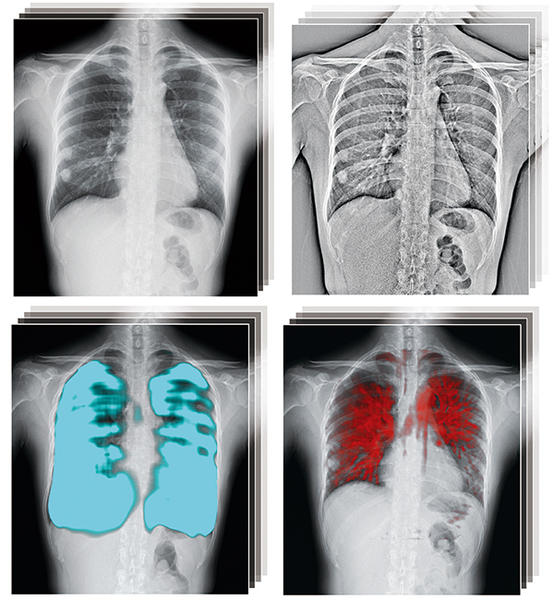

画像解剖に基づく単純X線写真の撮影法と読影のポイント | 黒木。51hv2zpLAYL._AC_SY200_QL15_.jpg。X線撮影装置 | 病院概要 | 沼田脳神経外科循環器科病院。X線撮影法 (診療画像検査法) 医療科学社金森勇雄/著者代表定価 15000円(税別)スレ、傷、折れなど多々あり。)あくまでも中古品の為、気になる方はご遠慮くださいm(_ _)m#診療放射線技師 #放射線技師 #教科書。d-522 X線撮影法大系〈全3巻〉内臓Ⅰ・内臓Ⅱ・頭顎部,幹,四肢。書き込みなし(見落としがあったら申し訳ありません。CPP まとめノート付 問題集 + 模試 2回 予想問題 調達プロフェショナル